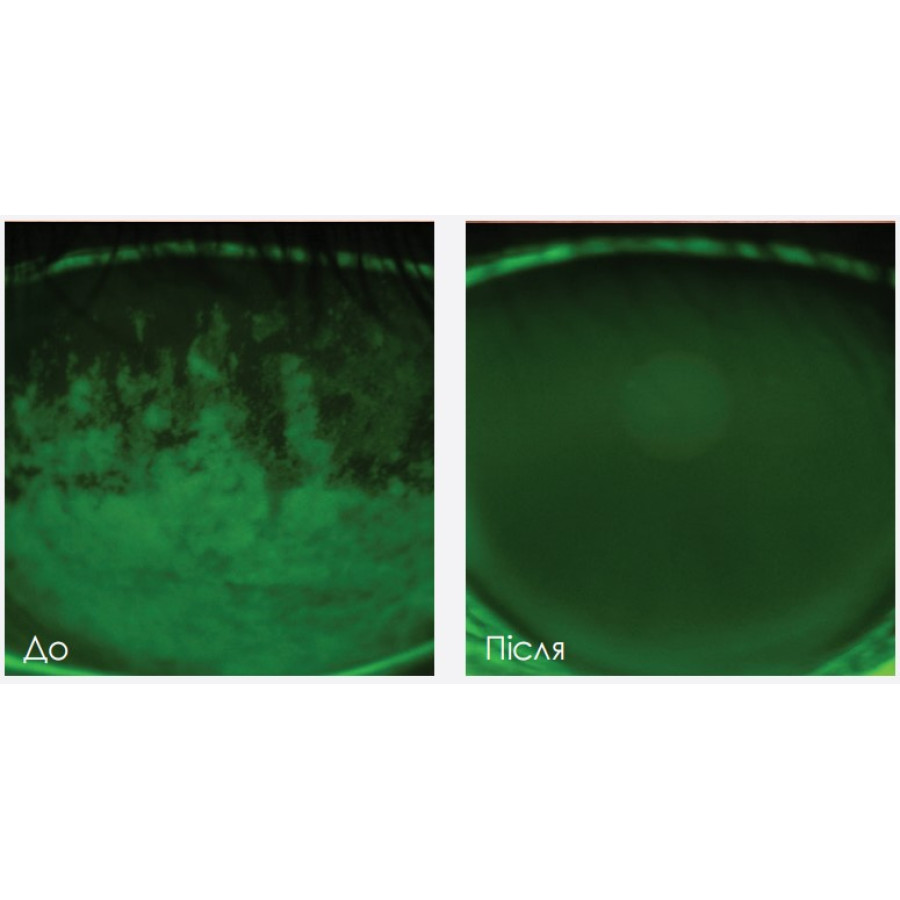

ДМЗ є головною причиною хвороби сухого ока та характеризується запаленням поверхні ока.

Forma-I був розроблений для усунення симптомів хвороби сухого ока, спричиненої дисфункцією мейбомієвої залози (МГЗ). Призначений для застосування в періорбітальній області, верхніх і нижніх століттях, знімає запалення мейбомієвих залоз і подразнення очей.

Компактна маніпула доводить температуру зони оброблення до оптимального рівня (43°C) та забезпечує комфортний, прецизійний та рівномірний нагрів тканин. Безкомпромісна безпечність, компактність маніпули, прецизійний контроль глибини впливу та розумний моніторинг перебігу процедури робить Forma-I прекрасним альтернативним методом лікування для мільйонів пацієнтів, що страждають на синдром сухого ока та ДМЗ.

Lumecca дозволено FDA для лікування доброякісних пігментних епідермальних уражень і доброякісних шкірних судинних уражень. Lumecca з адаптером Lumecca-I дозволяє виконувати прецизійні таргетовані процедури для лікування запалень найменших ділянок. Маніпула оптимізована для типів шкіри I-IV. Ксенонова лампа випромінює 40% загальної енергії спалаху у діапазоні 500-600 нм. Енергія IPL проникає у шкіру та селективно поглинається хромофорами в ураження (меланіном або гемоглобіном). Ця енергія перетворюється на тепло, відбувається селективна коагуляція уражень, які зникають протягом кількох тижнів. Клінічні дослідження довели ефективність IPL для лікування ДМЗ і синдрому сухого ока.